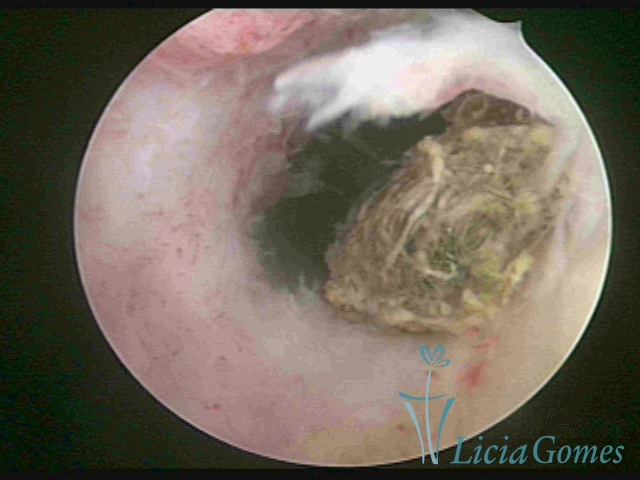

Cavidade uterina com DIU, envelhecido e dobrado